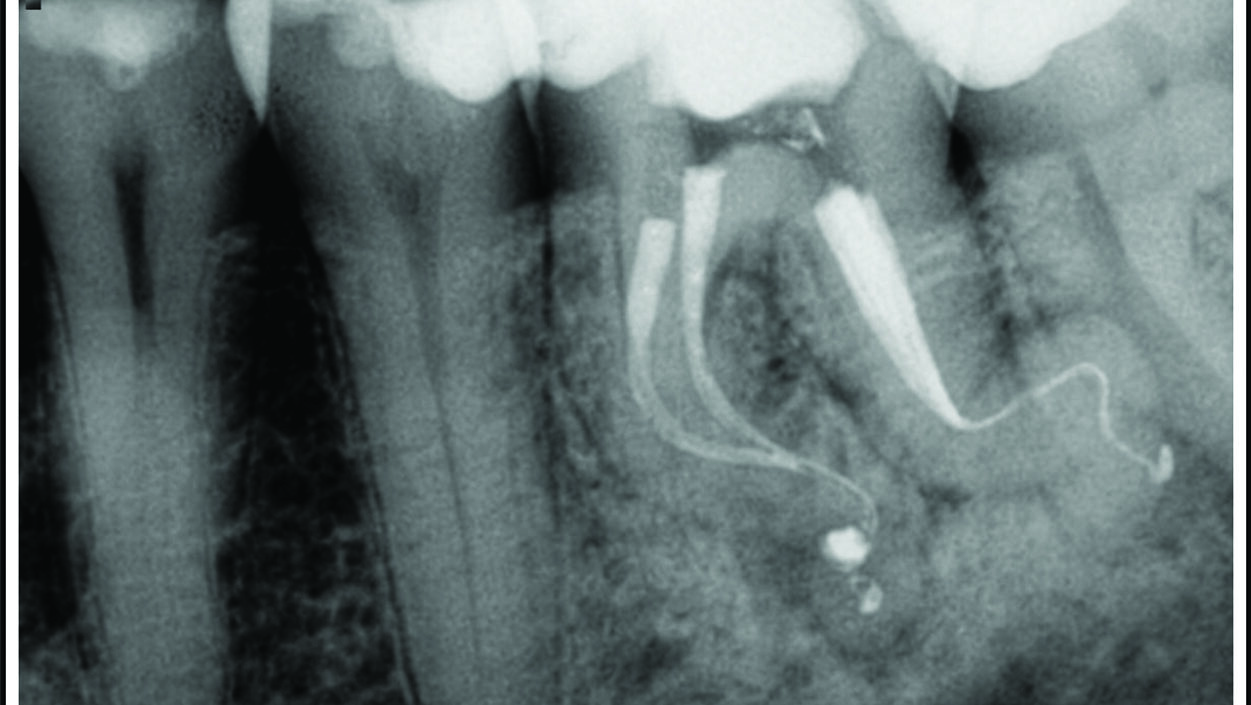

Safe and Effective 3-D Endodontic Disinfection: Laser Assisted Endodontic Irrigation

The ultimate goal of endodontic treatment is the prevention and/or treatment of apical periodontitis such that there is complete healing and absence of infection1 while the overall long-term goal is the placement of a definitive, clinically successful restoration and preservation of tooth structure. Successful endodontic treatment depends on a number of factors, including proper instrumentation, successful … Read more